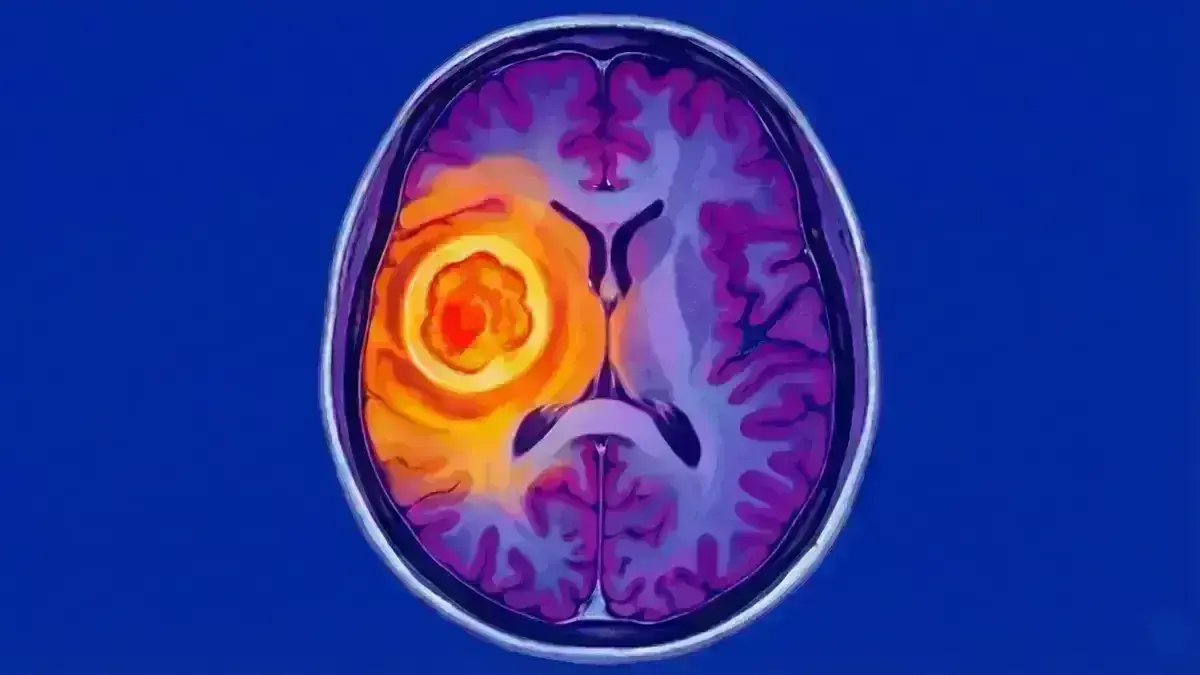

🧠 Abscesso Cerebral

> "Uma bolsa de pus dentro do cérebro — emergência que precisa de antibióticos e, muitas vezes, cirurgia imediata"

Uma bolsa (coleção) de pus — resultado de bactérias, fungos ou parasitas — que se formou dentro do tecido cerebral. Funciona como um "balão" ocupando espaço, comprimindo o cérebo e aumentando a pressão dentro da cabeça.